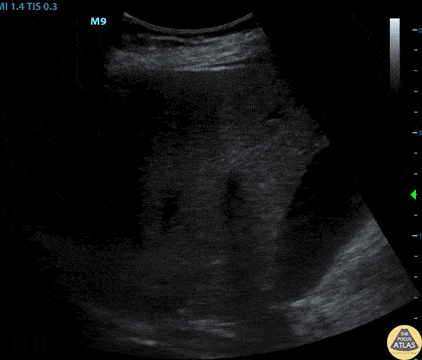

This image demonstrates an adrenal mass on the right kidney which was a known pheochromocytoma. Image courtesy of Cody McIlvain, MD. Resident, Emergency Medicine; Denver Health Residency in Emergency Medicine, Denver, Colorado.